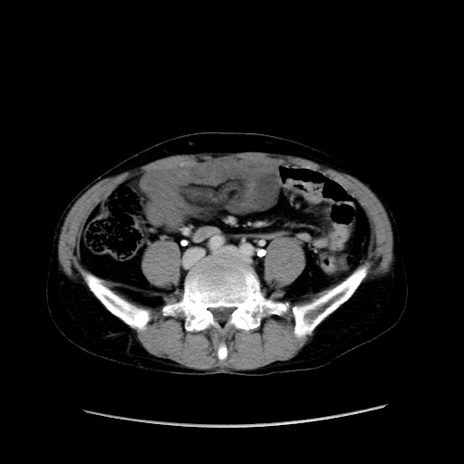

症例37(横断像)

【症例】40歳代 男性

【主訴】腹痛

【現病歴】4時間ほど前に電車に乗車中に臍部上より腹痛出現。徐々に増悪し起立困難となり、救急外来受診。生ものは数日食べていない。今朝お雑煮を食べた。

【身体所見】BT 36.8℃、BP 117/84mmHg、HR 91/min、SpO2 97%、苦悶様、腹部:臍上部広範囲圧痛あり、反跳痛±

【データ】WBC 8100、CRP 0.03